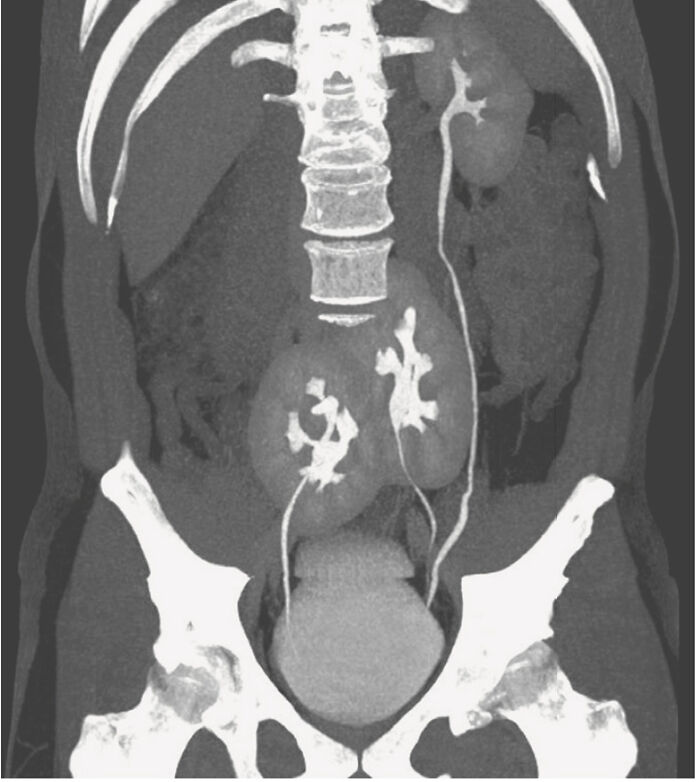

Went To Get A Scan For Practicing Medical Students (I Was A Volunteer Modle)

Didn't Expect To See I Have A Condition Where My Hearts Artery And Vein Has Been Flipped To The Opposite Sides Of Each Other At Birth, Which Is Apparently Rare.

I have a retroverted uterus! (Tilted backwards rather than forwards). It’s not super rare but not super common either. Doesn’t really mean anything, it’s not a medical issue, just a fun fact I learned during my last pelvic exam 😅